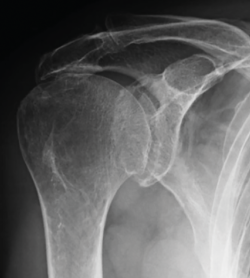

Las roturas que no se deben reparar son aquellas en las que encontramos una subluxación superior de la cabeza humeral en la que la distancia acromiohumeral es inferior a 7 mm o bien exista una artropatía glenohumeral tipo 2 de Hamada o superior(7)(Figura 1), y aquellas en las que hay una infiltración grasa de grados III/IV de los músculos supra- y/o infraespinoso(8).

Figura 1. Subluxación fija de la cabeza humeral (distancia acromiohumeral < 7 mm).